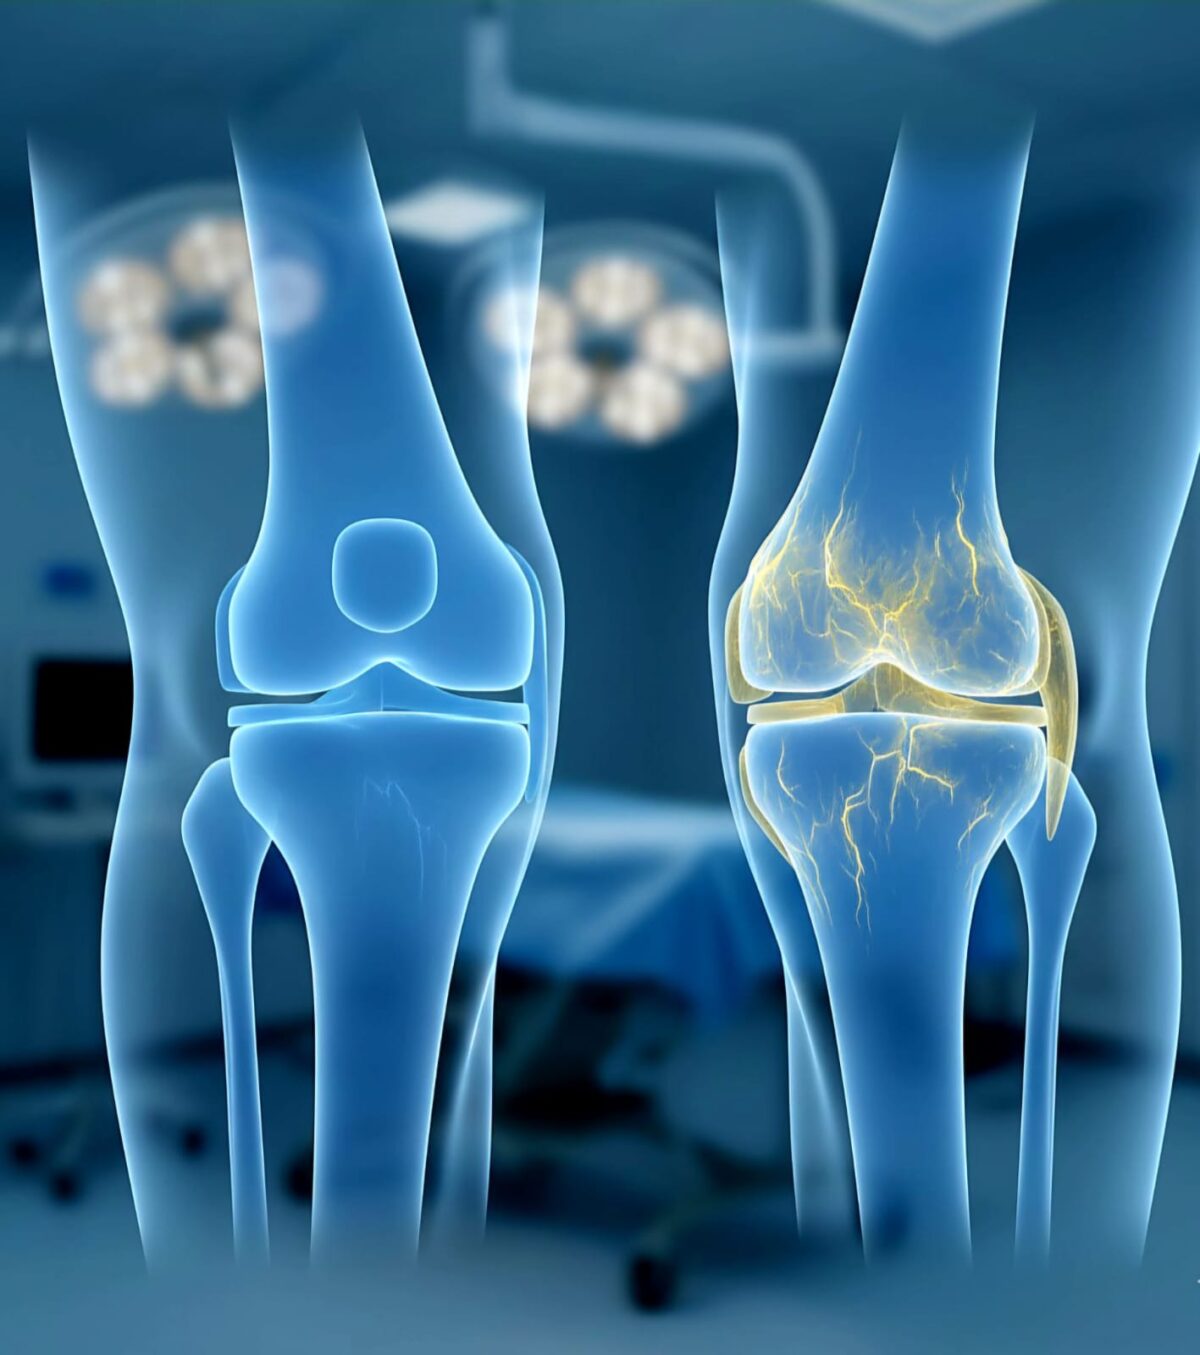

2 - أسئلة وأجوبة جراحة العظام والمفاصل المتعلقة بالركبة والمنظار

استعد حريتك في الحركة: دليلك الشامل لتغيير مفاصل الركبة والورك مع د. أحمد سلام

يعاني الملايين من خشونة المفاصل المتقدمة التي تجعل من مجرد المشي أو الصلاة عبئاً ثقيلاً. ولكن مع التطور الهائل في جراحات المفاصل الصناعية، لم يعد الألم قدراً محتوماً.

متى أحتاج إلى عملية تغيير مفصل الركبة؟

عندما تفشل كافة الحلول التحفظية والدوائية وتصبح خشونة الركبة عائقاً عن ممارسة أبسط الأنشطة اليومية.

كم يعيش مفصل الركبة الصناعي؟

هل يمكن الصلاة والسجود بعد تغيير مفصل الركبة؟

نستخدم مفاصل متطورة تسمح بمدى حركة واسع (High-Flex)، ولكن القدرة على السجود الكامل تختلف حسب حالة كل مريض.